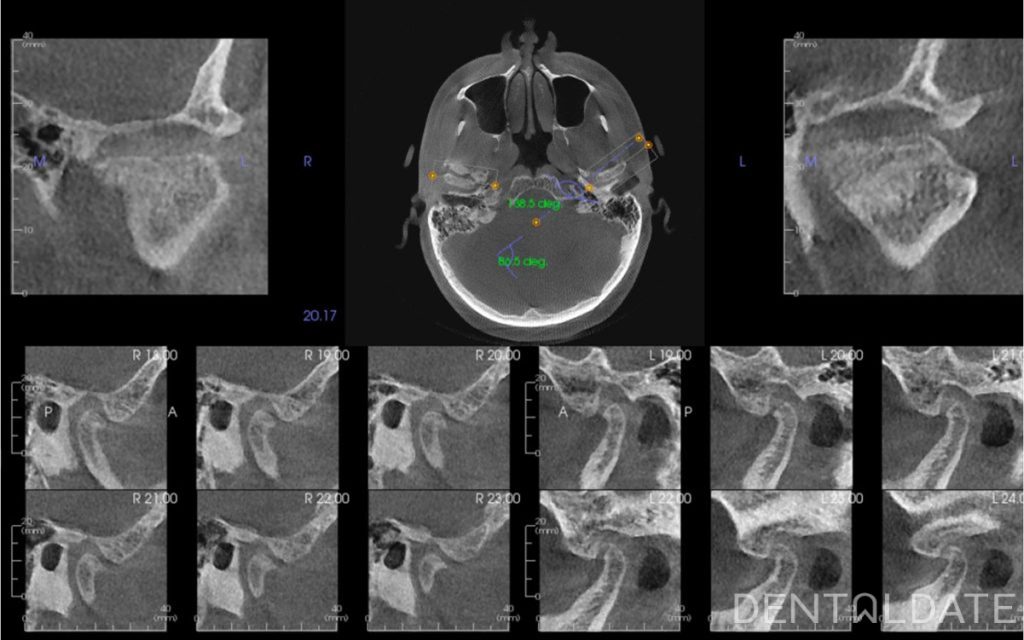

To correct the position of the lower jaw, we used a custom-made splint designed based on condylography results. Just five days after starting therapy, the patient reported complete relief from all previous symptoms, including significant posture improvement and reduced muscle tension.